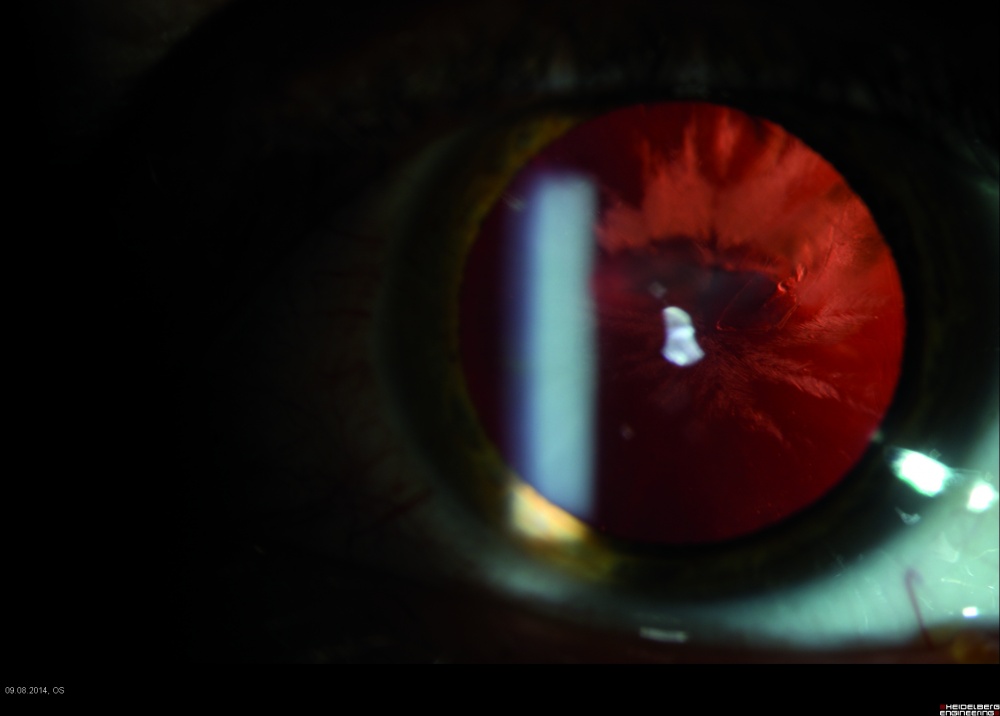

Bei der Inspektion der vorderen und hinteren Augenabschnitte zeigte sich eine zentrale 3 mm lange Penetrationsstelle der Hornhaut (Abbildung 1), eine Verletzung der vorderen und hinteren Linsenkapsel mit einer traumatischen Sekundärkatarakt (Abbildung 2) und ein im mittleren Glaskörperraum liegender metallischer Fremdkörper (Abbildung 3). Der Visus am betroffenen Auge betrug 0,2 und am Partnerauge 1,0 ohne Korrektion.

Die Ultraschalldiagnostik zeigte den klinisch (Abbildung 4) gut sichtbaren Fremdkörper im mittleren Glaskörperraum lokalisiert. Die Untersuchung des Augenhintergrundes zeigte keine Verletzung der Netzhaut. Es wurde deshalb auf eine Röntgen(CT)- Diagnostik verzichtet.